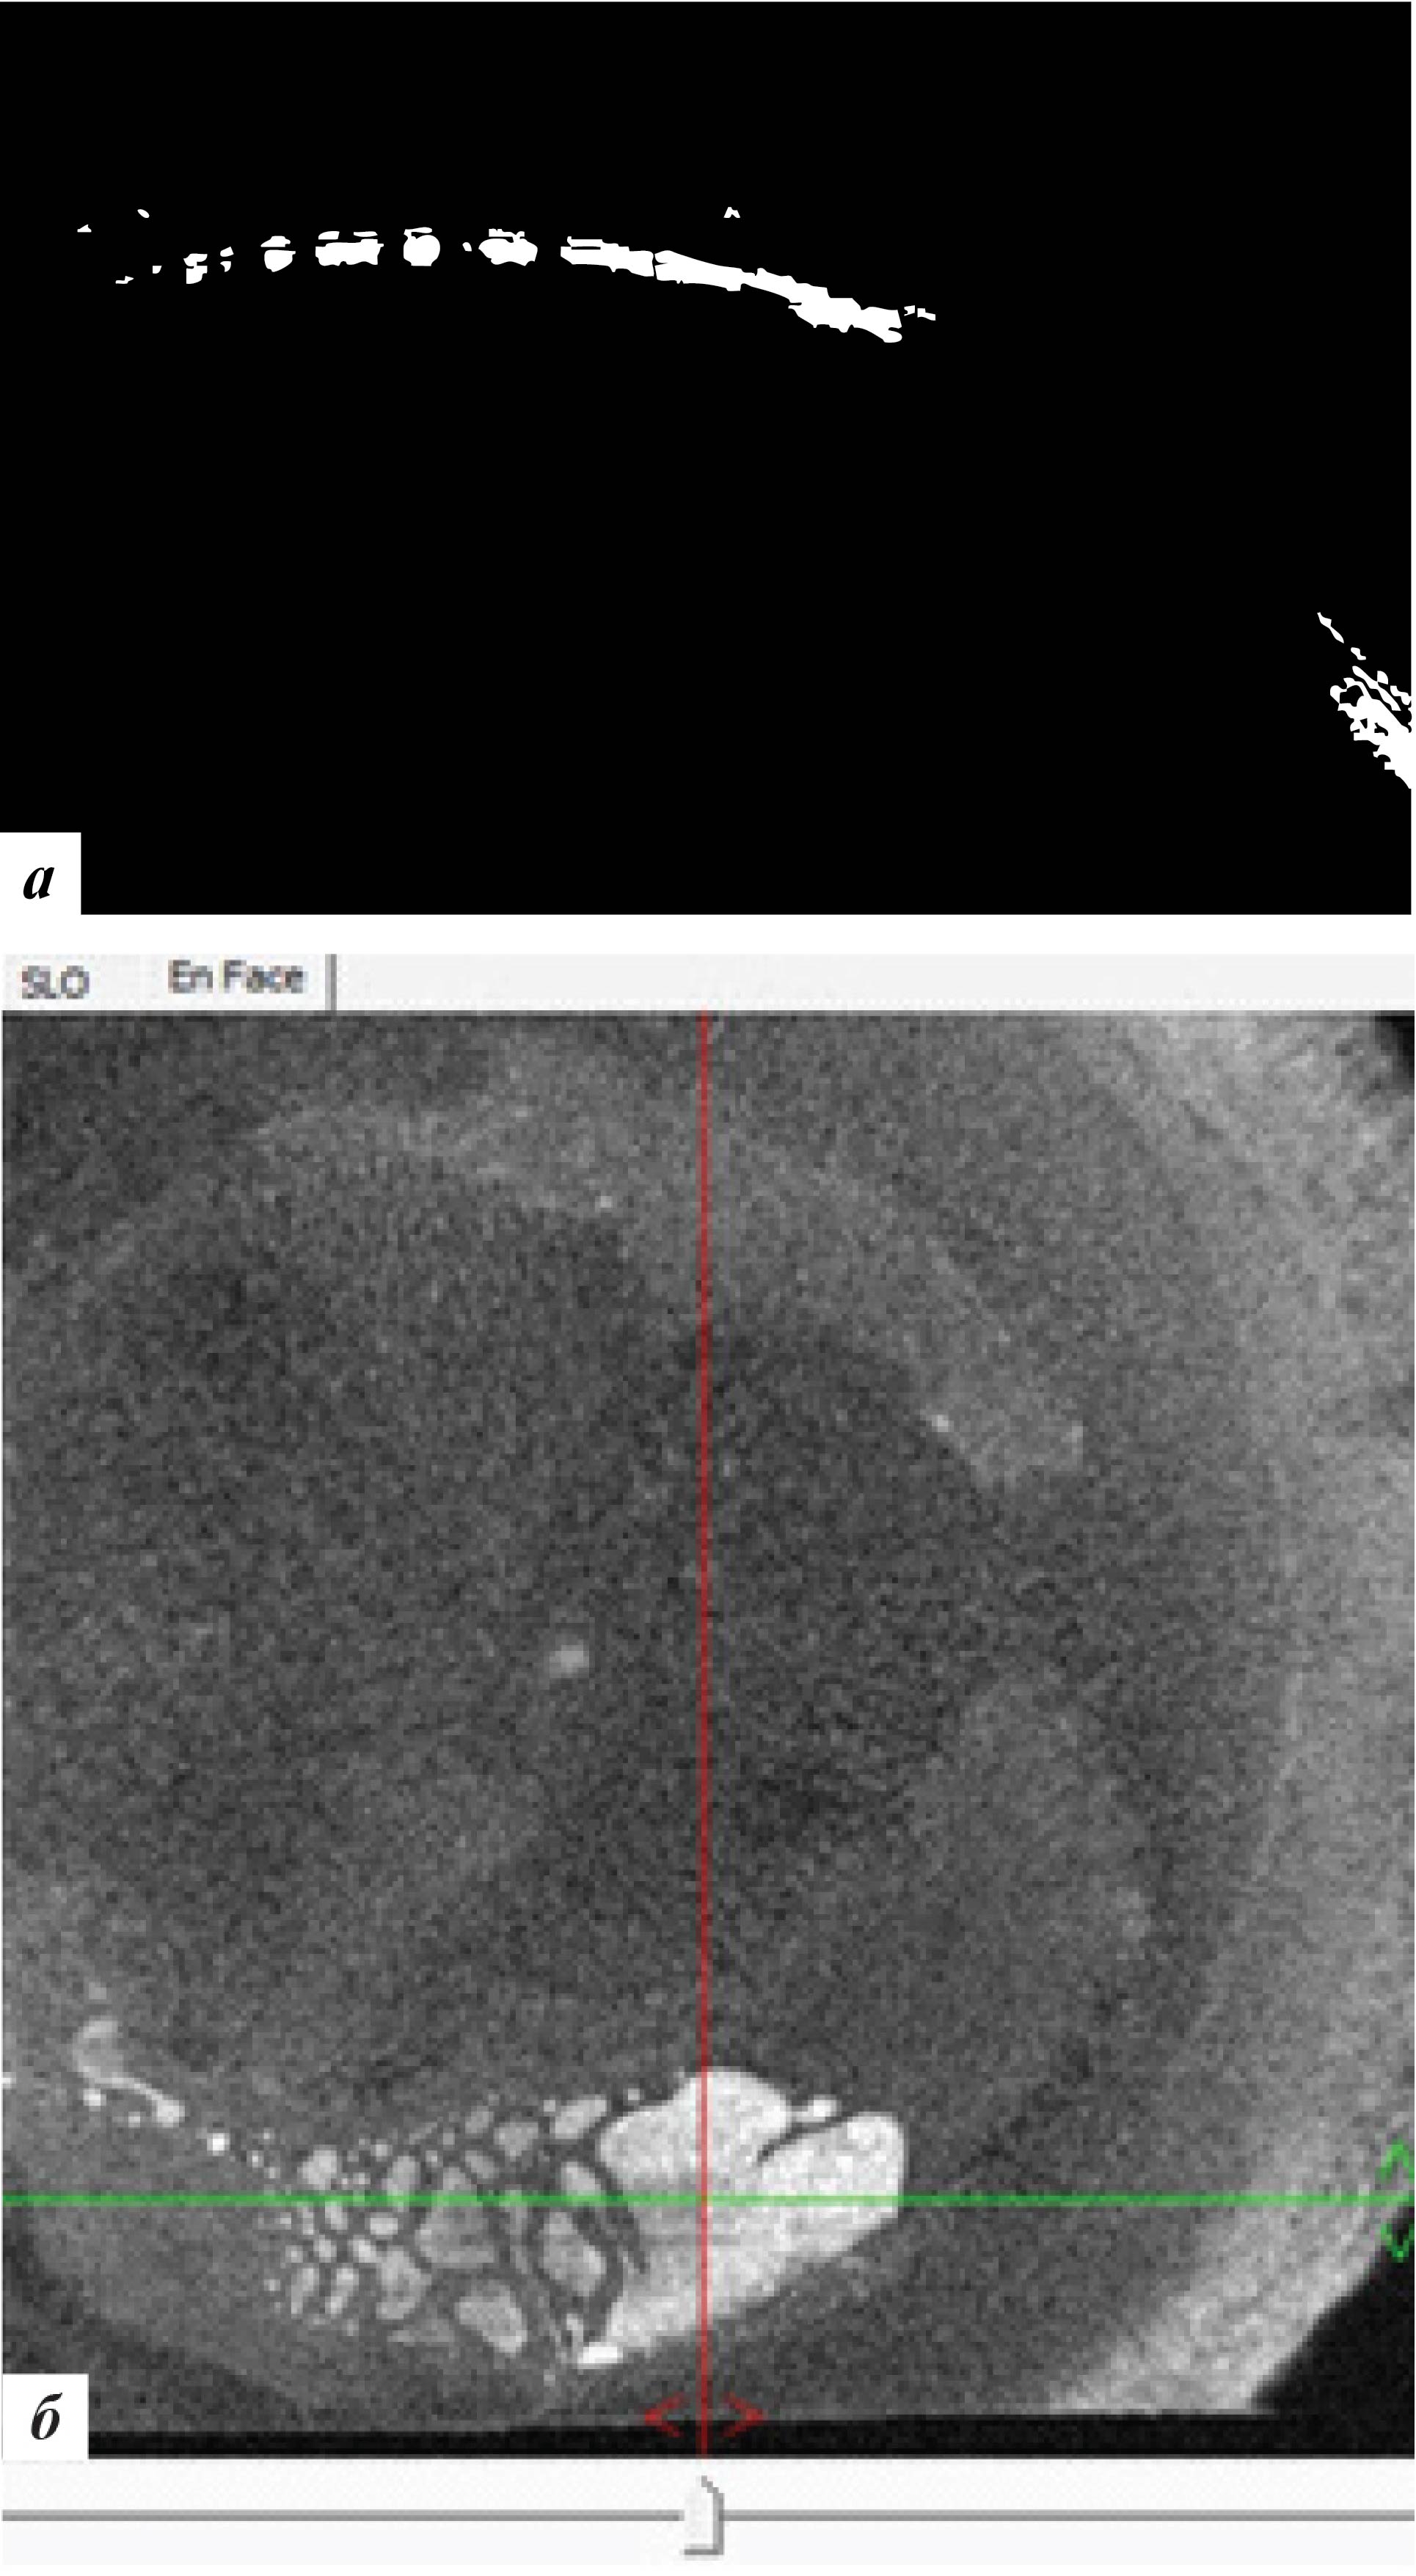

Высота вросшего эпителия по данным ОКТ роговицы уменьшилась (рис. 7). Пациентке было рекомендовано продолжение наблюдения.

Рис. 7. Данные ОКТ роговицы левого глаза через 3 месяца после лечения: а – горизонтальная проекция, б – фронтальная проекция

Рис. 9. Данные ОКТ роговицы левого глаза через 9 месяцев после лечения: а – горизонтальная проекция, б – фронтальная проекция